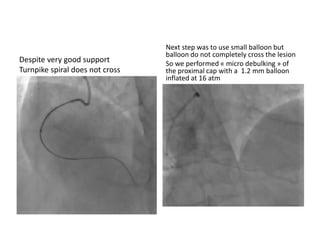

Despite very good support

Turnpike spiral does not cross

Next step was to use small balloon but

balloon do not completely cross the lesion

So we performed « micro debulking » of

the proximal cap with a 1.2 mm balloon

inflated at 16 atm